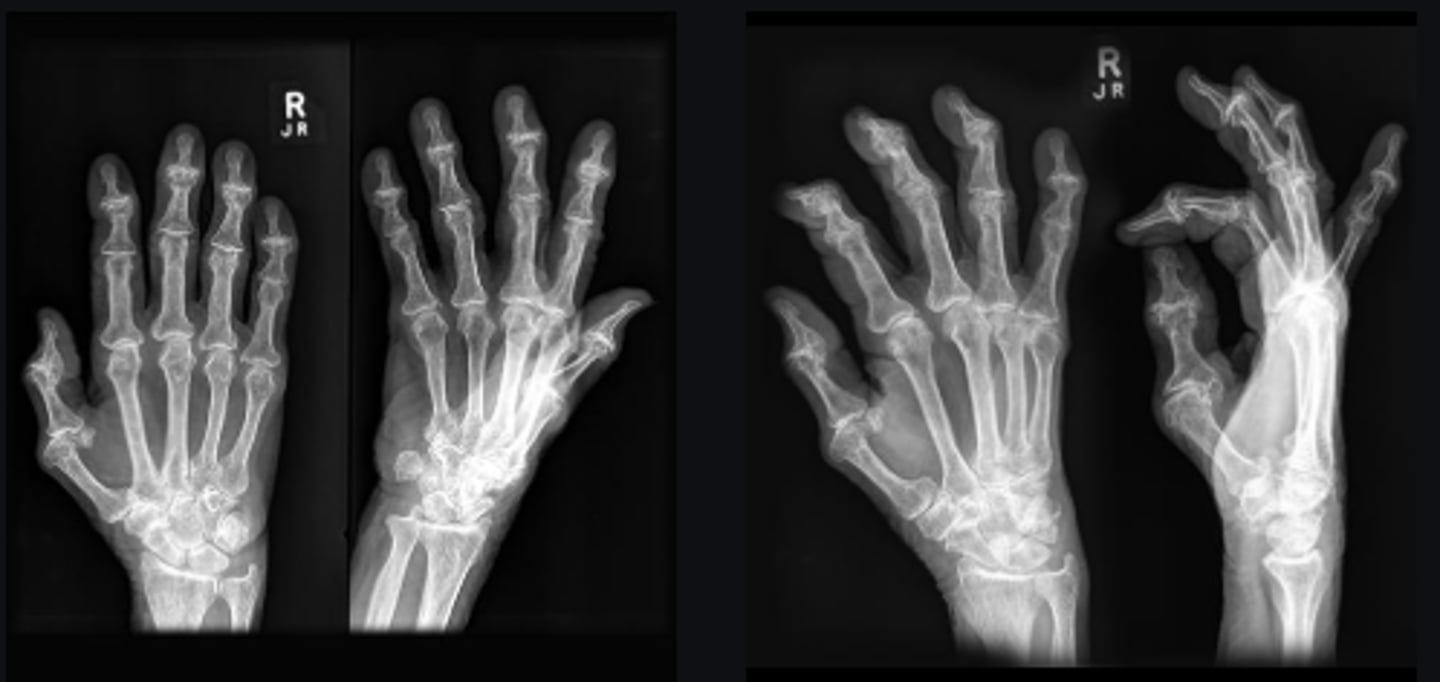

1st metarcarpal and trapezium

Bone

Carpometacarpal joint

Joint

Yes

Joint space narrowed?

No

Periarticular erosions

Osteophytes

Subchondral cysts

Subchondral sclerosis

Periarticular osteopenia

Soft tissue swelling

Intra-articular calcification

Joint ankylosis

Extra-articular calcification/osseous bodies

Subluxation

Dislocation/diastasis

Unilateral

Bilateral/unilateral

Degenerative

Category of disease

Osteoarthrosis

Diagnosis?

Correlate with patient

Next step?